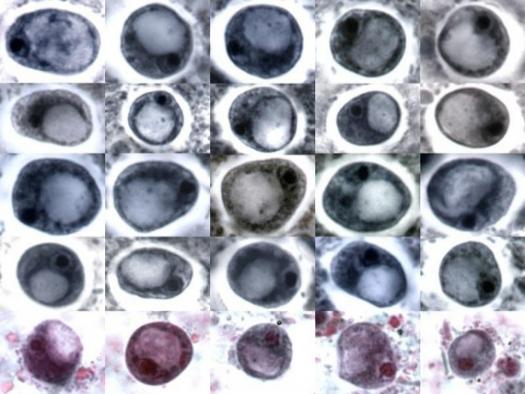

24. Completely identify the name and stage of the parasite. Wrong spelling is wrong. Incomplete answers will be incorrect as well. (e.g. Entamoeba coli cyst)

The correct answer is Entamoeba histolytica cyst. Entamoeba histolytica is a parasite that causes amoebic dysentery and other intestinal infections in humans. The cyst stage is the infective form of the parasite that is able to survive outside the host and can be transmitted through contaminated food or water. Identifying the correct name and stage of the parasite is crucial for accurate diagnosis and treatment of the infection.